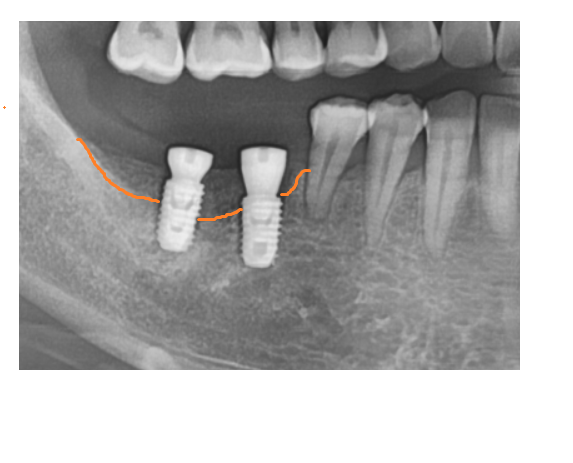

임플란트는 심었지만

주황색 선 위쪽으로는 뼈가 충분하지 않아요~

뼈가 충분한 아래쪽은 밀도가 높아 좀 더 하얀색이죠~?